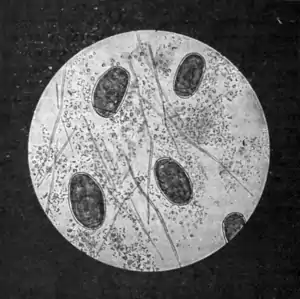

The sputum.— On placing a minute portion of the viscid, pneumonic-like sputum under the microscope, its peculiar colour is found to be due partly to red blood-corpuscles, partly to a crowd of dark- brown, thick-shelled, operculated ova (Fig. 161). These ova vary a good deal in size and shape; they are all distinctly oval, have a yellow, smooth, double-outlined shell, and measure from 80 to 100 μ. in length by 40 to 60 μ in breadth. If the sputum be shaken up in water, and the water be renewed from time to time, in the course of a month or six weeks— longer or shorter according to temperature a ciliated miracidium is developed in each ovum. When the ovum is mature, on placing it on a slide and exercising slight pressure on the cover-glass the operculum will be forced back, and the miracidium will immediately emerge and begin to swim about and gyrate in the water.

Fig. 161.—Ova of Paragonimus westermani in sputum.